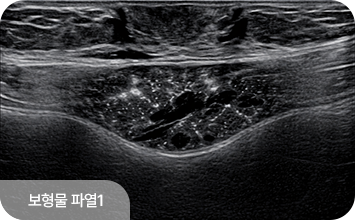

유방 확대술(보형물 삽입) 후에도 초음파 검진은 동일하게 시행할 수 있으며,

보형물 위의 유방 조직을 꼼꼼히 관찰하여 종괴나 이상 소견을 확인합니다.

보형물 자체의 파열이나 누출 여부도 초음파로 평가할 수 있어,

수술 후에도 정기적인 초음파 검진이 중요합니다.